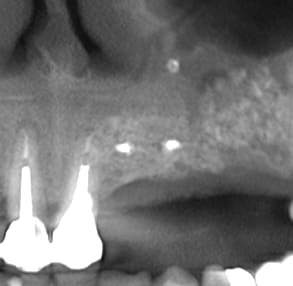

26/04/2010 à 14h00

la suite radiologique du cas, implantation prévu le 6 mai

Biobank   6 mois dbkbbo - Eugenol

Biobank 6 mois  2 cj54ky - Eugenol

Biobank 6mois 3 ck56hx - Eugenol

Biobank 6 mois 4 giwlus - Eugenol

Post1 y45ukn - Eugenol

Post2 caxl5b - Eugenol

Post3 ovhzhy - Eugenol

par contre en distal qualité du TO ? ce qui corrélerait bien l'impression au scanner par rapport à la densité .

en distal, bonne densité de forage (plus dur en tout cas que l'aspect pourrait le faire penser).